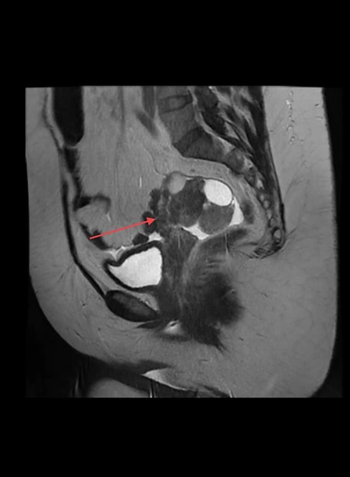

A 50-year-old female patient, asymptomatic, in a routine gynecological medical consultation, was requested to perform a transvaginal ultrasonography, which revealed an enlarged right ovary, showing regular contours and heterogeneous echotexture due to the presence of a nodular, heterogeneous, predominantly echogenic image, with areas of posterior acoustic shadow measuring approximately 3.2 x 3.1 cm. Dermoid cyst was questioned by the ultrasonographer and recommended further investigation with MRI. The patient underwent the suggested examination within a few days and the right ovary was found to be enlarged, displaced posteriorly, measuring approximately 7 x 5.6 x 2.8 cm, associated with the presence of simple cystic formations measuring up to 3.2 cm and one with thick content measuring 2.1 cm (Figure 1 and 2). It is also noted the presence of two hypovascular nodular formations in between, with heterogeneous signal, in close proximity to the serosa of the right lateral uterine body wall, measuring 4.5 x 3.1 cm.

Figure 2 Right adnexal mass sagittal plane in MRI demonstrated by red arrow.